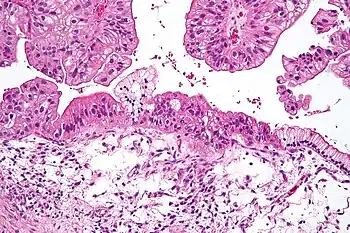

| Micrograph of a mucinous ovarian carcinoma stained by H&E | |

Mucinous tumors include mucinous adenocarcinoma and mucinous cystadenocarcinoma.[29]

Mucinous adenocarcinoma

Mucinous adenocarcinomas make up 5–10% of epithelial ovarian cancers. Histologically, they are similar to intestinal or cervical adenocarcinomas and are often actually metastases of appendiceal or colon cancers. Advanced mucinous adenocarcinomas have a poor prognosis, generally worse than serous tumors, and are often resistant to platinum chemotherapy, though they are rare.[29]